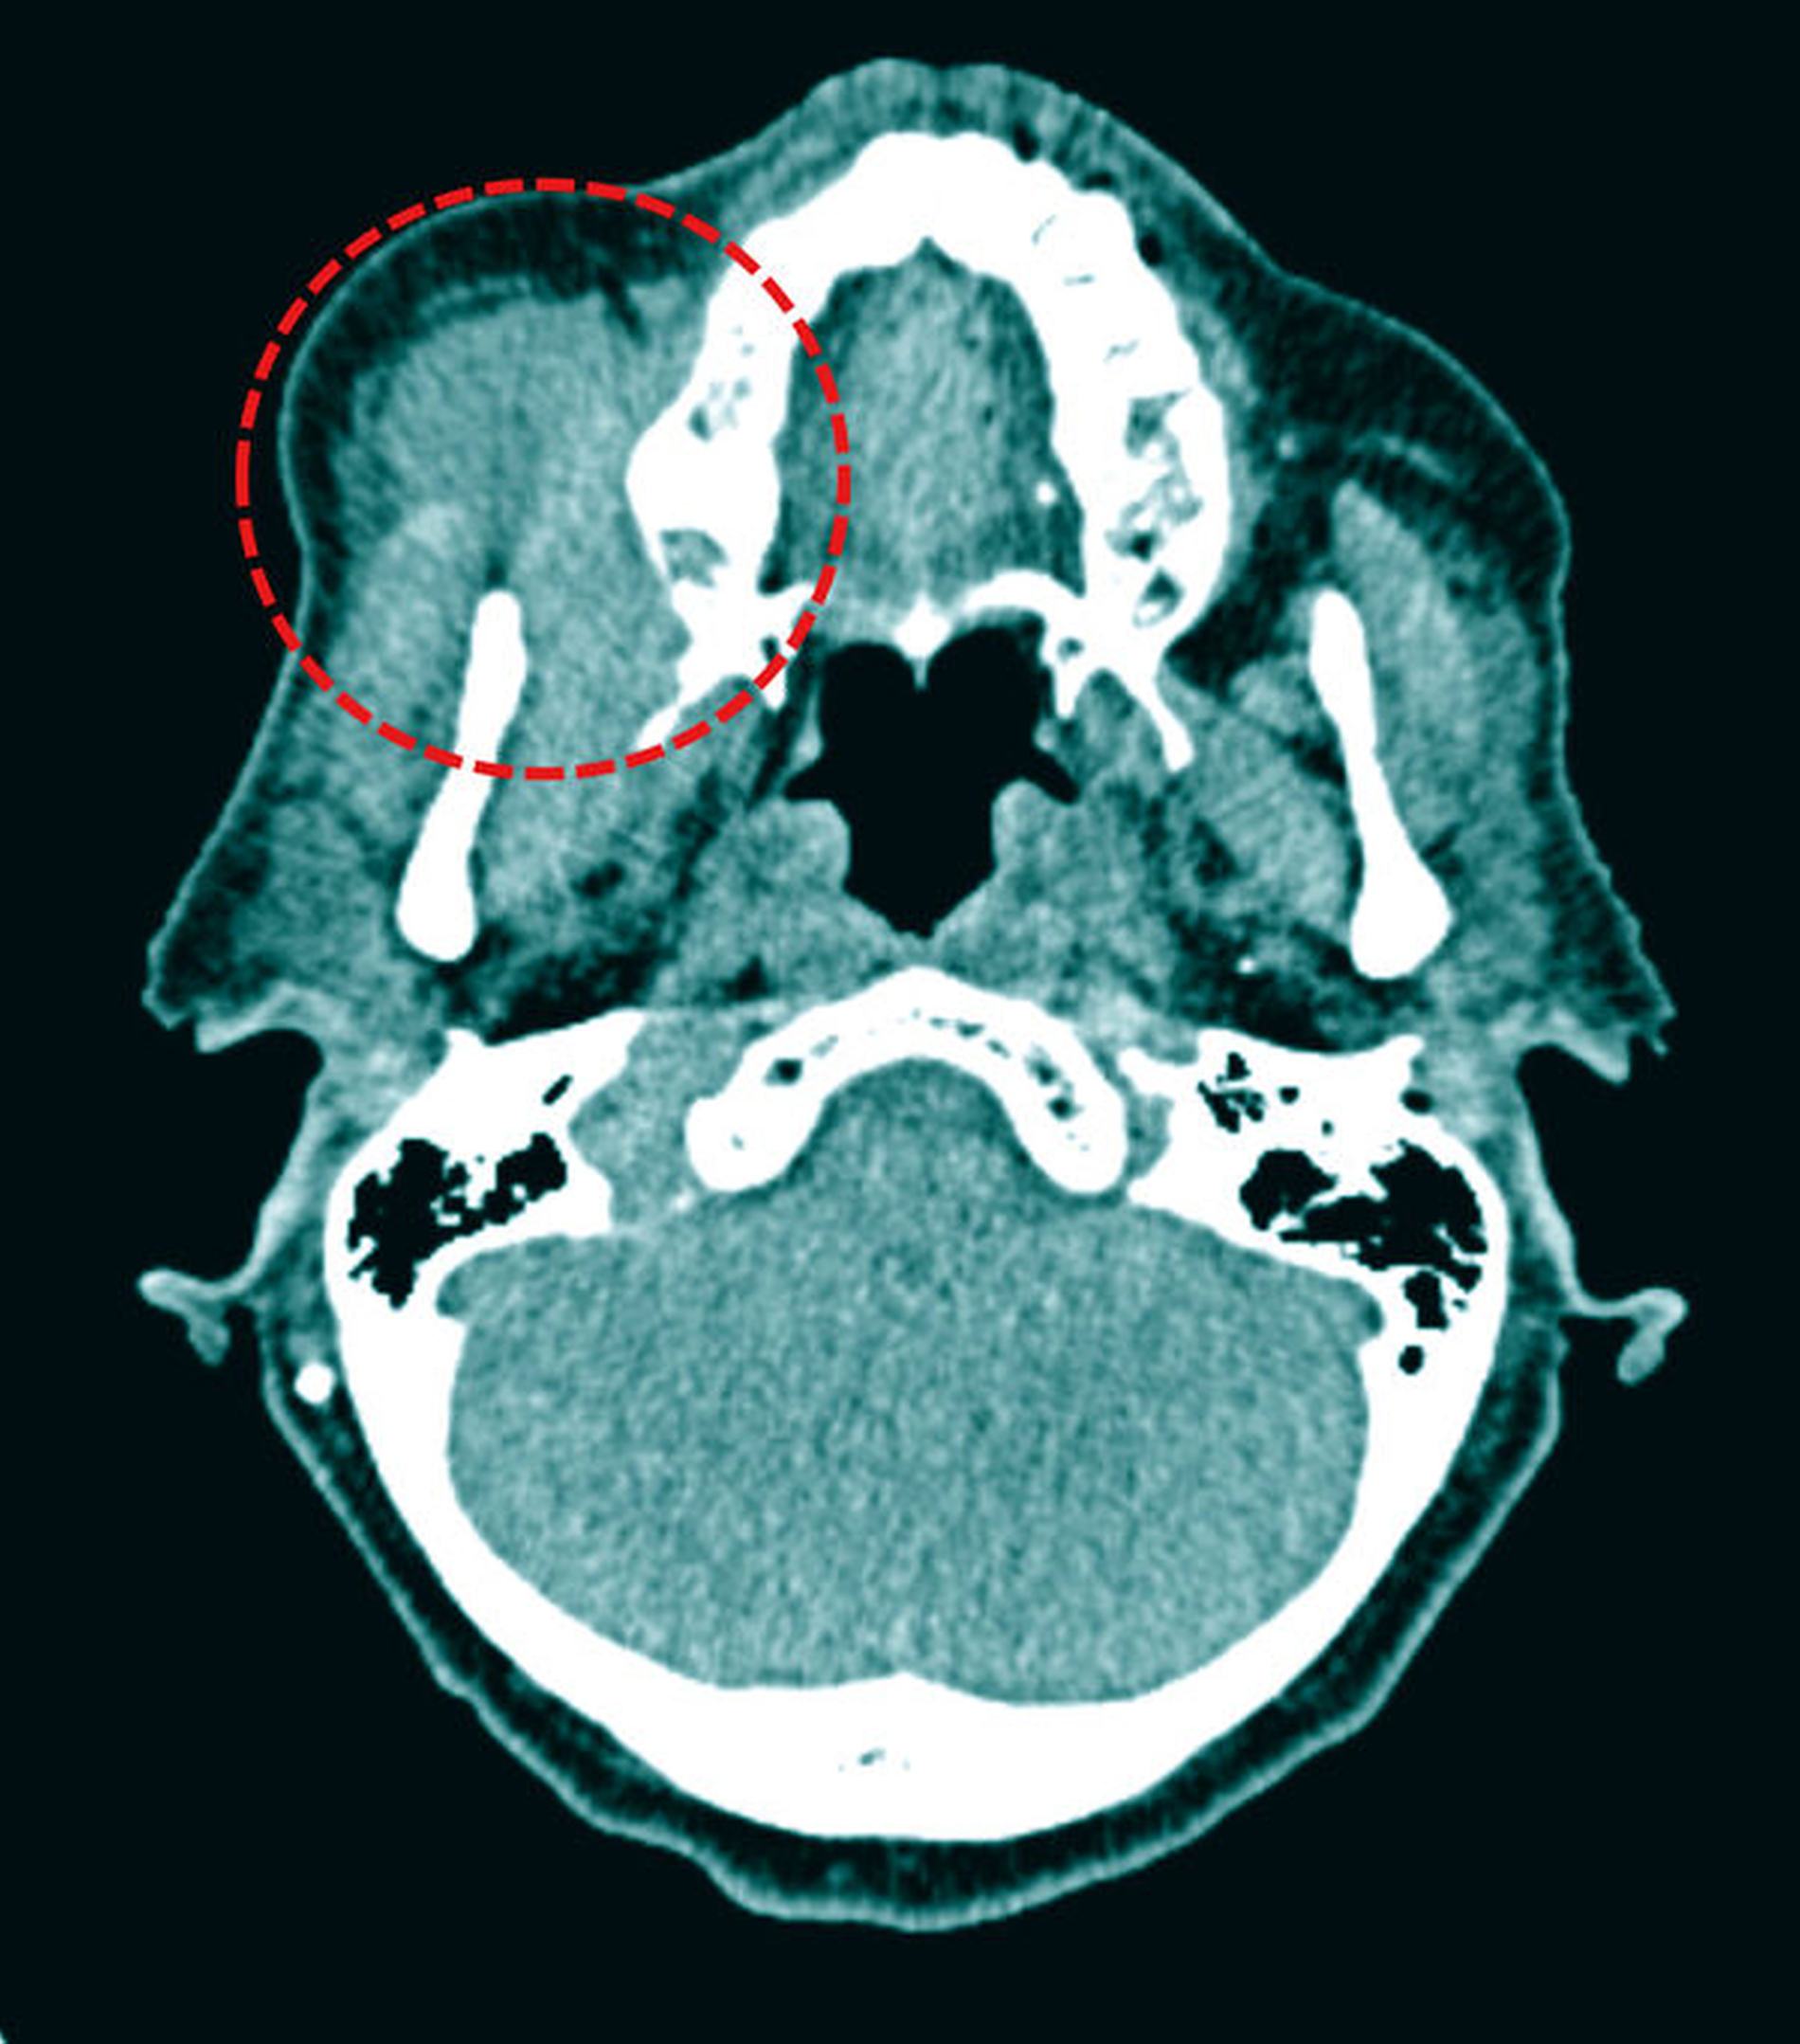

In der CT-Untersuchung mit Kontrastmittel zeigte sich eine ausgedehnte Raumforderung der rechten Wange, die keinerlei klare Infiltration oder Destruktion der anatomischen Nachbarstrukturen aufwies (Abbildung 3). Zur weiteren Diagnostik erfolgte in Lokalanästhesie von intraoral eine Probenentnahme. Im histologischen Präparat zeigte sich ein diffuses, sich ausbreitendes Infiltrat aus mittelgroßen, runden Blasten im fibrösen Weichgewebe und Fett ohne eine erhaltene Lymphknotenstruktur.